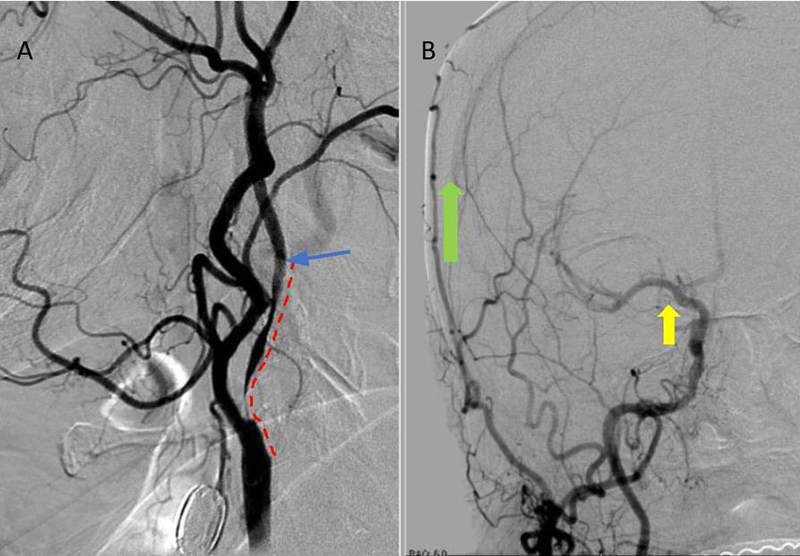

Under Monitored Anesthesia Care, and systemic anticoagulation (ACT maintained above 250), a 6 French Guide Sheath was positioned within the distal cervical right Common Carotid Artery (CCA). Slow antegrade filling of the right internal carotid, MCA, and ACA was observed compatible with flow limitation, as well as physiologic need for this relatively isolated circulation. In addition, primary embolic protection filter placement was not considered technically feasible secondary to the severity of the “string” like stenosis. Serial primary angioplasty with 2 x 20 mm and a 2.5 x 20 mm balloon was gently performed to 10-12 ATM, creating an improved channel within the stenosis. An exchange length .014 (300 cm) “buddy” wire was then positioned across the lesion to maintain access, as an embolic protection filter was carefully navigated and deployed in the distal cervical ICA. Subsequently, a 4 x 40 mm PTA balloon was then utilized to perform angioplasty with embolic protection, followed by placement of a 40 mm stent tapering from 6 to 8 mm from distal to proximal within the right ICA and CCA. Post Stenting angiography demonstrates no significant residual stenosis with significantly enhanced right hemispheric perfusion on angiography (Figure 5).

Figure 5. A) Pre-Dilatation with 2.5 x 20mm balloon (arrow) ; B) Initial PTA result with “Buddy Wire”; C) final Post PTA and Stent with no significant residual stenosis across the entire length of the atherosclerotic segment (dotted).